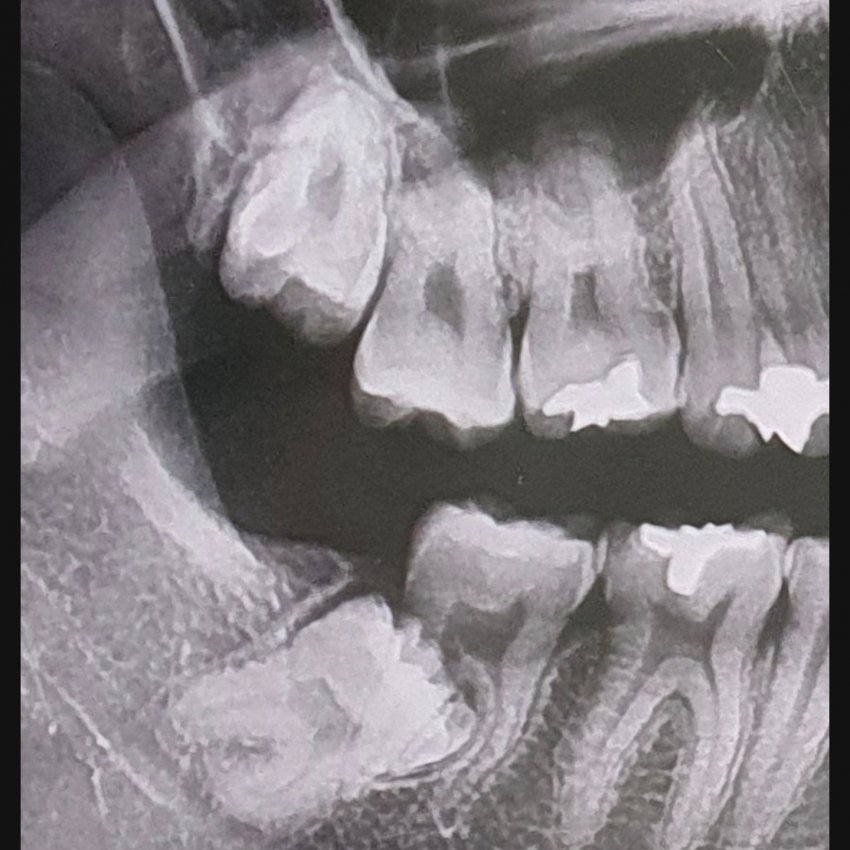

3.

BWoLNe

서울대 병원가서 뽑음.